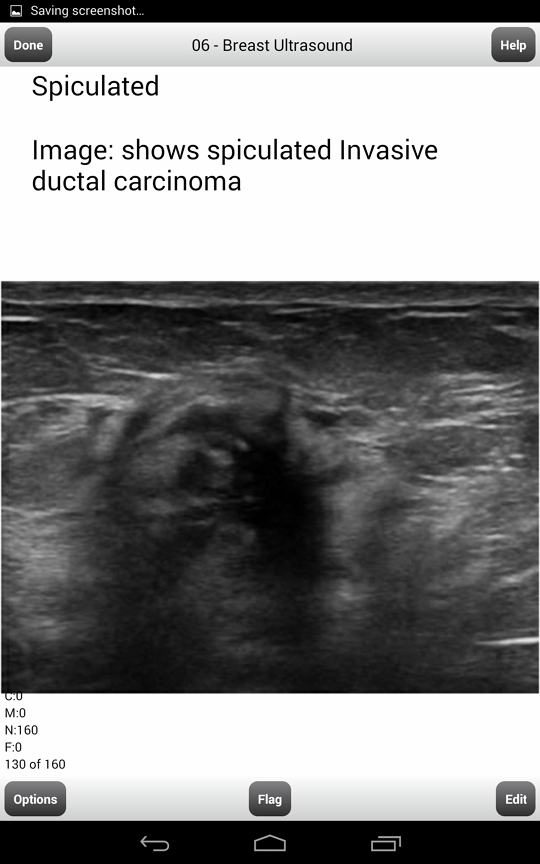

A Review Of Breast Ultrasound - Penn Medicine

Attenuation of ultrasound by solid masses can cause intense shadowing and obscure breast anatomy posterior to the lesion. Also, breast structures like connective tissues and ... Fetch This Document